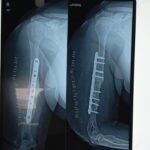

Dr Sagar aim for early mobilization after trauma surgery. We also take care of total aseptic precaution with implants.

Complex trauma surgery is required for severe injuries such as multiple fractures, joint injuries, open fractures, or injuries involving previous implants or deformities. These cases need advanced surgical techniques, careful planning, and specialized orthopedic expertise. The aim of trauma and complex trauma surgery is to promote proper healing, restore movement, and help patients return to daily activities safely.